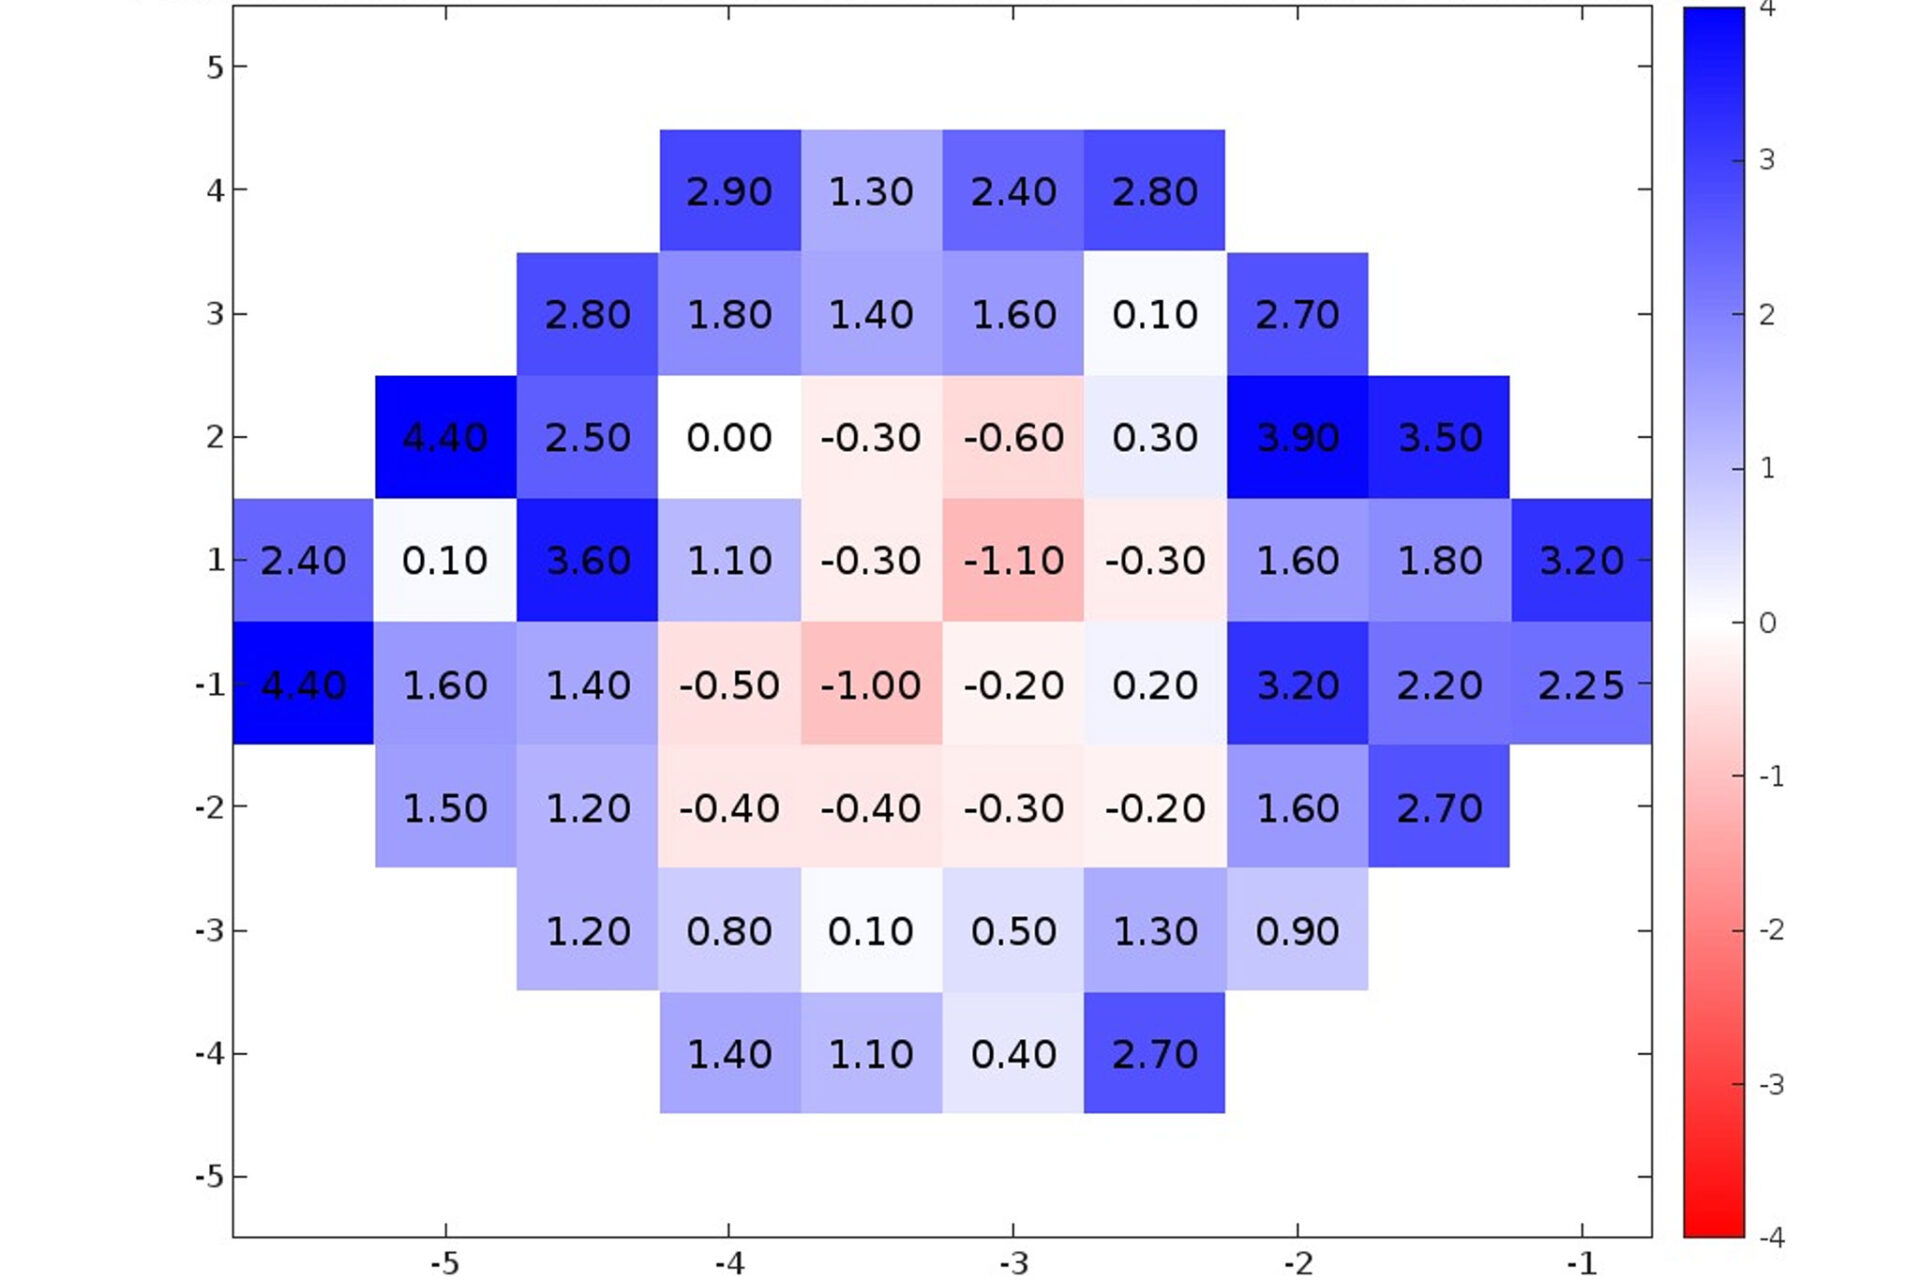

Advancing Ocular Diagnostics: A Comparative Study Between the RVF100 Portable Virtual Reality Device and the Humphrey Visual Field Analyzer for Glaucoma Suspect Assessment

An ARVO 2024 study comparing the RetinaLogik RVF100 to the Humphrey Visual Field Analyzer in glaucoma suspect evaluations found strong correlation across all key metrics (MD, PSD, MS), with performance comparable to gold-standard testing—supporting VR perimetry as a validated, portable, and cost-effective alternative. (ARVO 2024)

Advancing Ocular Diagnostics: A Comparative Study Between the RVF100 Portable Virtual Reality Device and the Humphrey Visual Field Analyzer for Glaucoma Suspect Assessment

An ARVO 2024 study comparing the RetinaLogik RVF100 to the Humphrey Visual Field Analyzer in glaucoma suspect evaluations found strong correlation across all key metrics (MD, PSD, MS), with performance comparable to gold-standard testing—supporting VR perimetry as a validated, portable, and cost-effective alternative. (ARVO 2024)